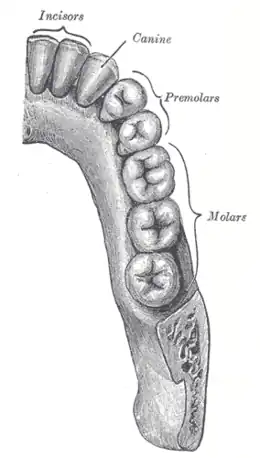

En anatomie, les prémolaires (ou dents prémolaires) font partie des dents postérieures de la denture des mammifères. Ce sont les plus antérieures des dents postérieures.

Un humain possède huit prémolaires : quatre supérieures et quatre inférieures. Les quatre plus médiales sont les premières prémolaires et les plus latérales sont les deuxièmes prémolaires.

Elles sont situées entre les canines et la première molaire définitive.

Leur couronne possède deux cuspides . Les deuxièmes prémolaires ne possèdent qu'une racine et les premières prémolaires possèdent généralement deux racines.